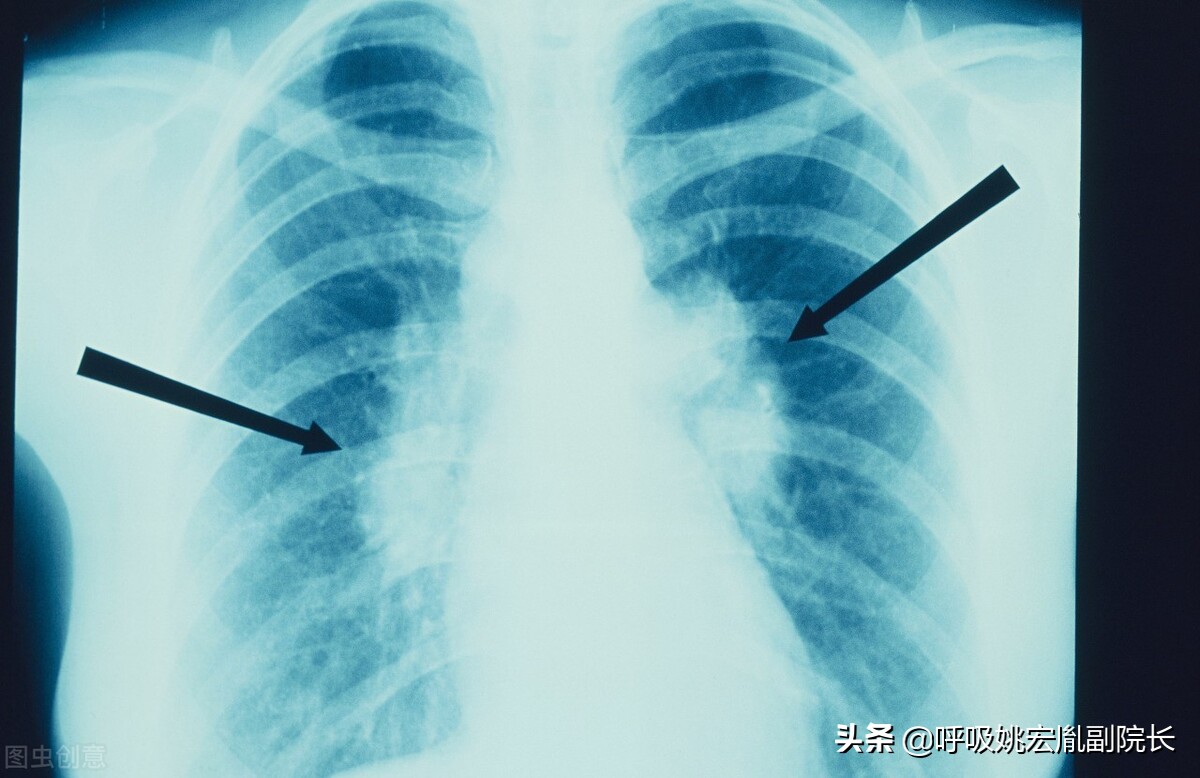

肺结节:

肺结节是指在肺实质内而不属于正常肺组织的结节状阴影,直径小于3厘米,其中直径小于1厘米的称之为小结节,直径小于3毫米的称之为微结节,而大于3厘米的我们称之为肿块。肺结节可以表现为单独一个,也可以是多个。80%-90%以上的肺结节都是良性的,当然也有一部分结节是恶性的,而少数肺良性结节在随访的过程中可能会出现恶变。